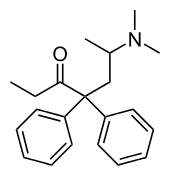

The first fully synthetic opioid was meperidine (later demerol), found serendipitously by German chemist Otto Eisleb (or Eislib) at IG Farben in 1932.[228] Meperidine was the first opiate to have a structure unrelated to morphine, but with opiate-like properties.[199] Its analgesic effects were discovered by Otto Schaumann in 1939.[228] Gustav Ehrhart and Max Bockmühl, also at IG Farben, built on the work of Eisleb and Schaumann. They developed "Hoechst 10820" (later methadone) around 1937.[230] In 1959 the Belgian physician Paul Janssen developed fentanyl, a synthetic drug with 30 to 50 times the potency of heroin.[211][231] Nearly 150 synthetic opioids are now known.[228]